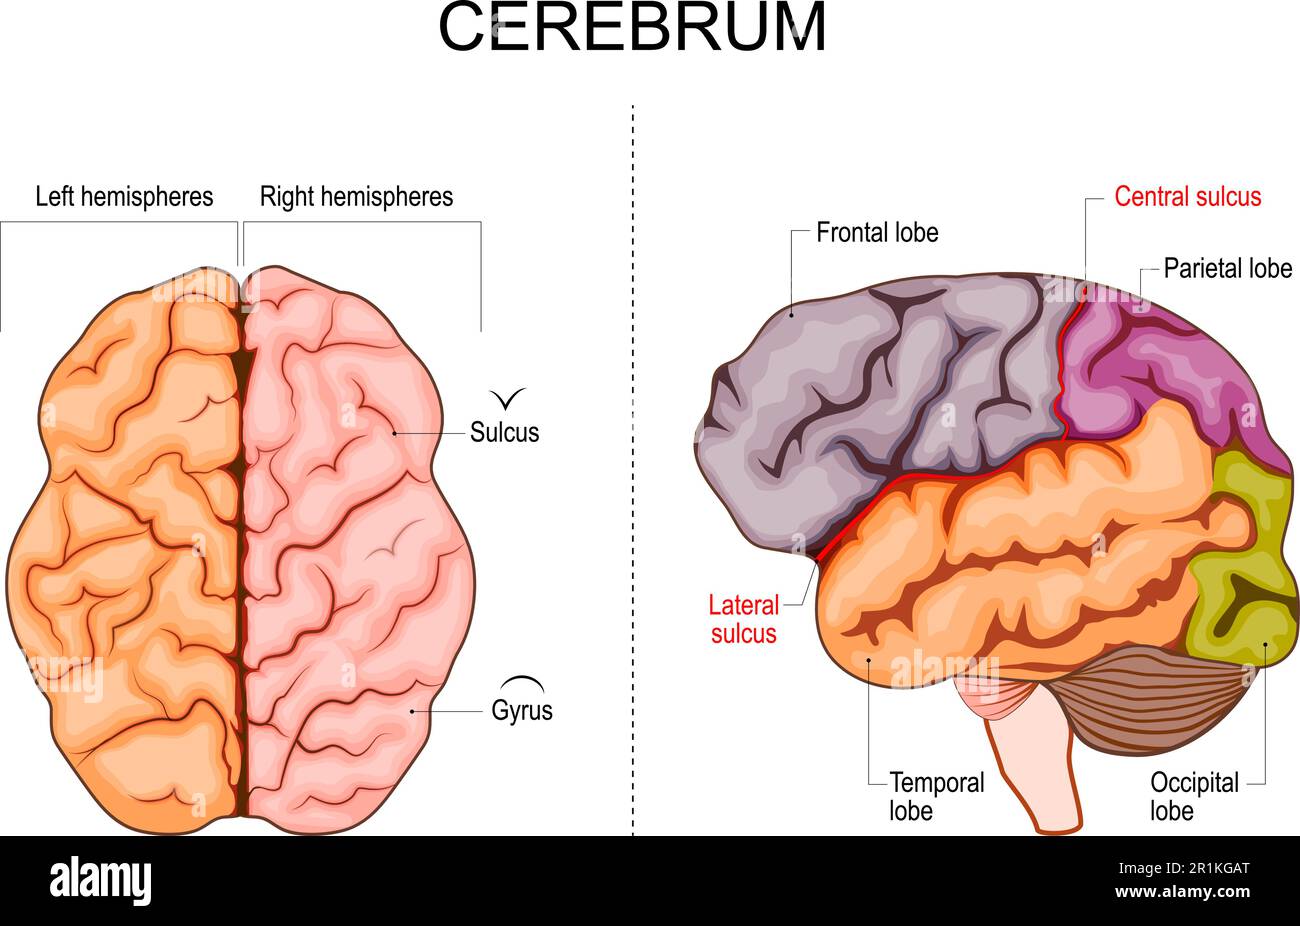

RF2R1KGAT–Struttura cerebrale umana. Emisferi e lobi della corteccia cerebrale. lobi frontali, temporali, occipitali e parietali. vista laterale e superiore

RF2Y8XEWG–Anatomia del cervello umano. Emisferi cerebrali, corteccia cerebrale, frontale, parietale, temporale, lobi occipitali, cervelletto e tronco cerebrale, fessura cerebrale.

RF2MXH9WX–Anatomia cerebrale umana Set di colori di viste laterali e anteriori superiori della corteccia cerebrale con giro cerebrale isolato su fondo bianco illust vettoriale